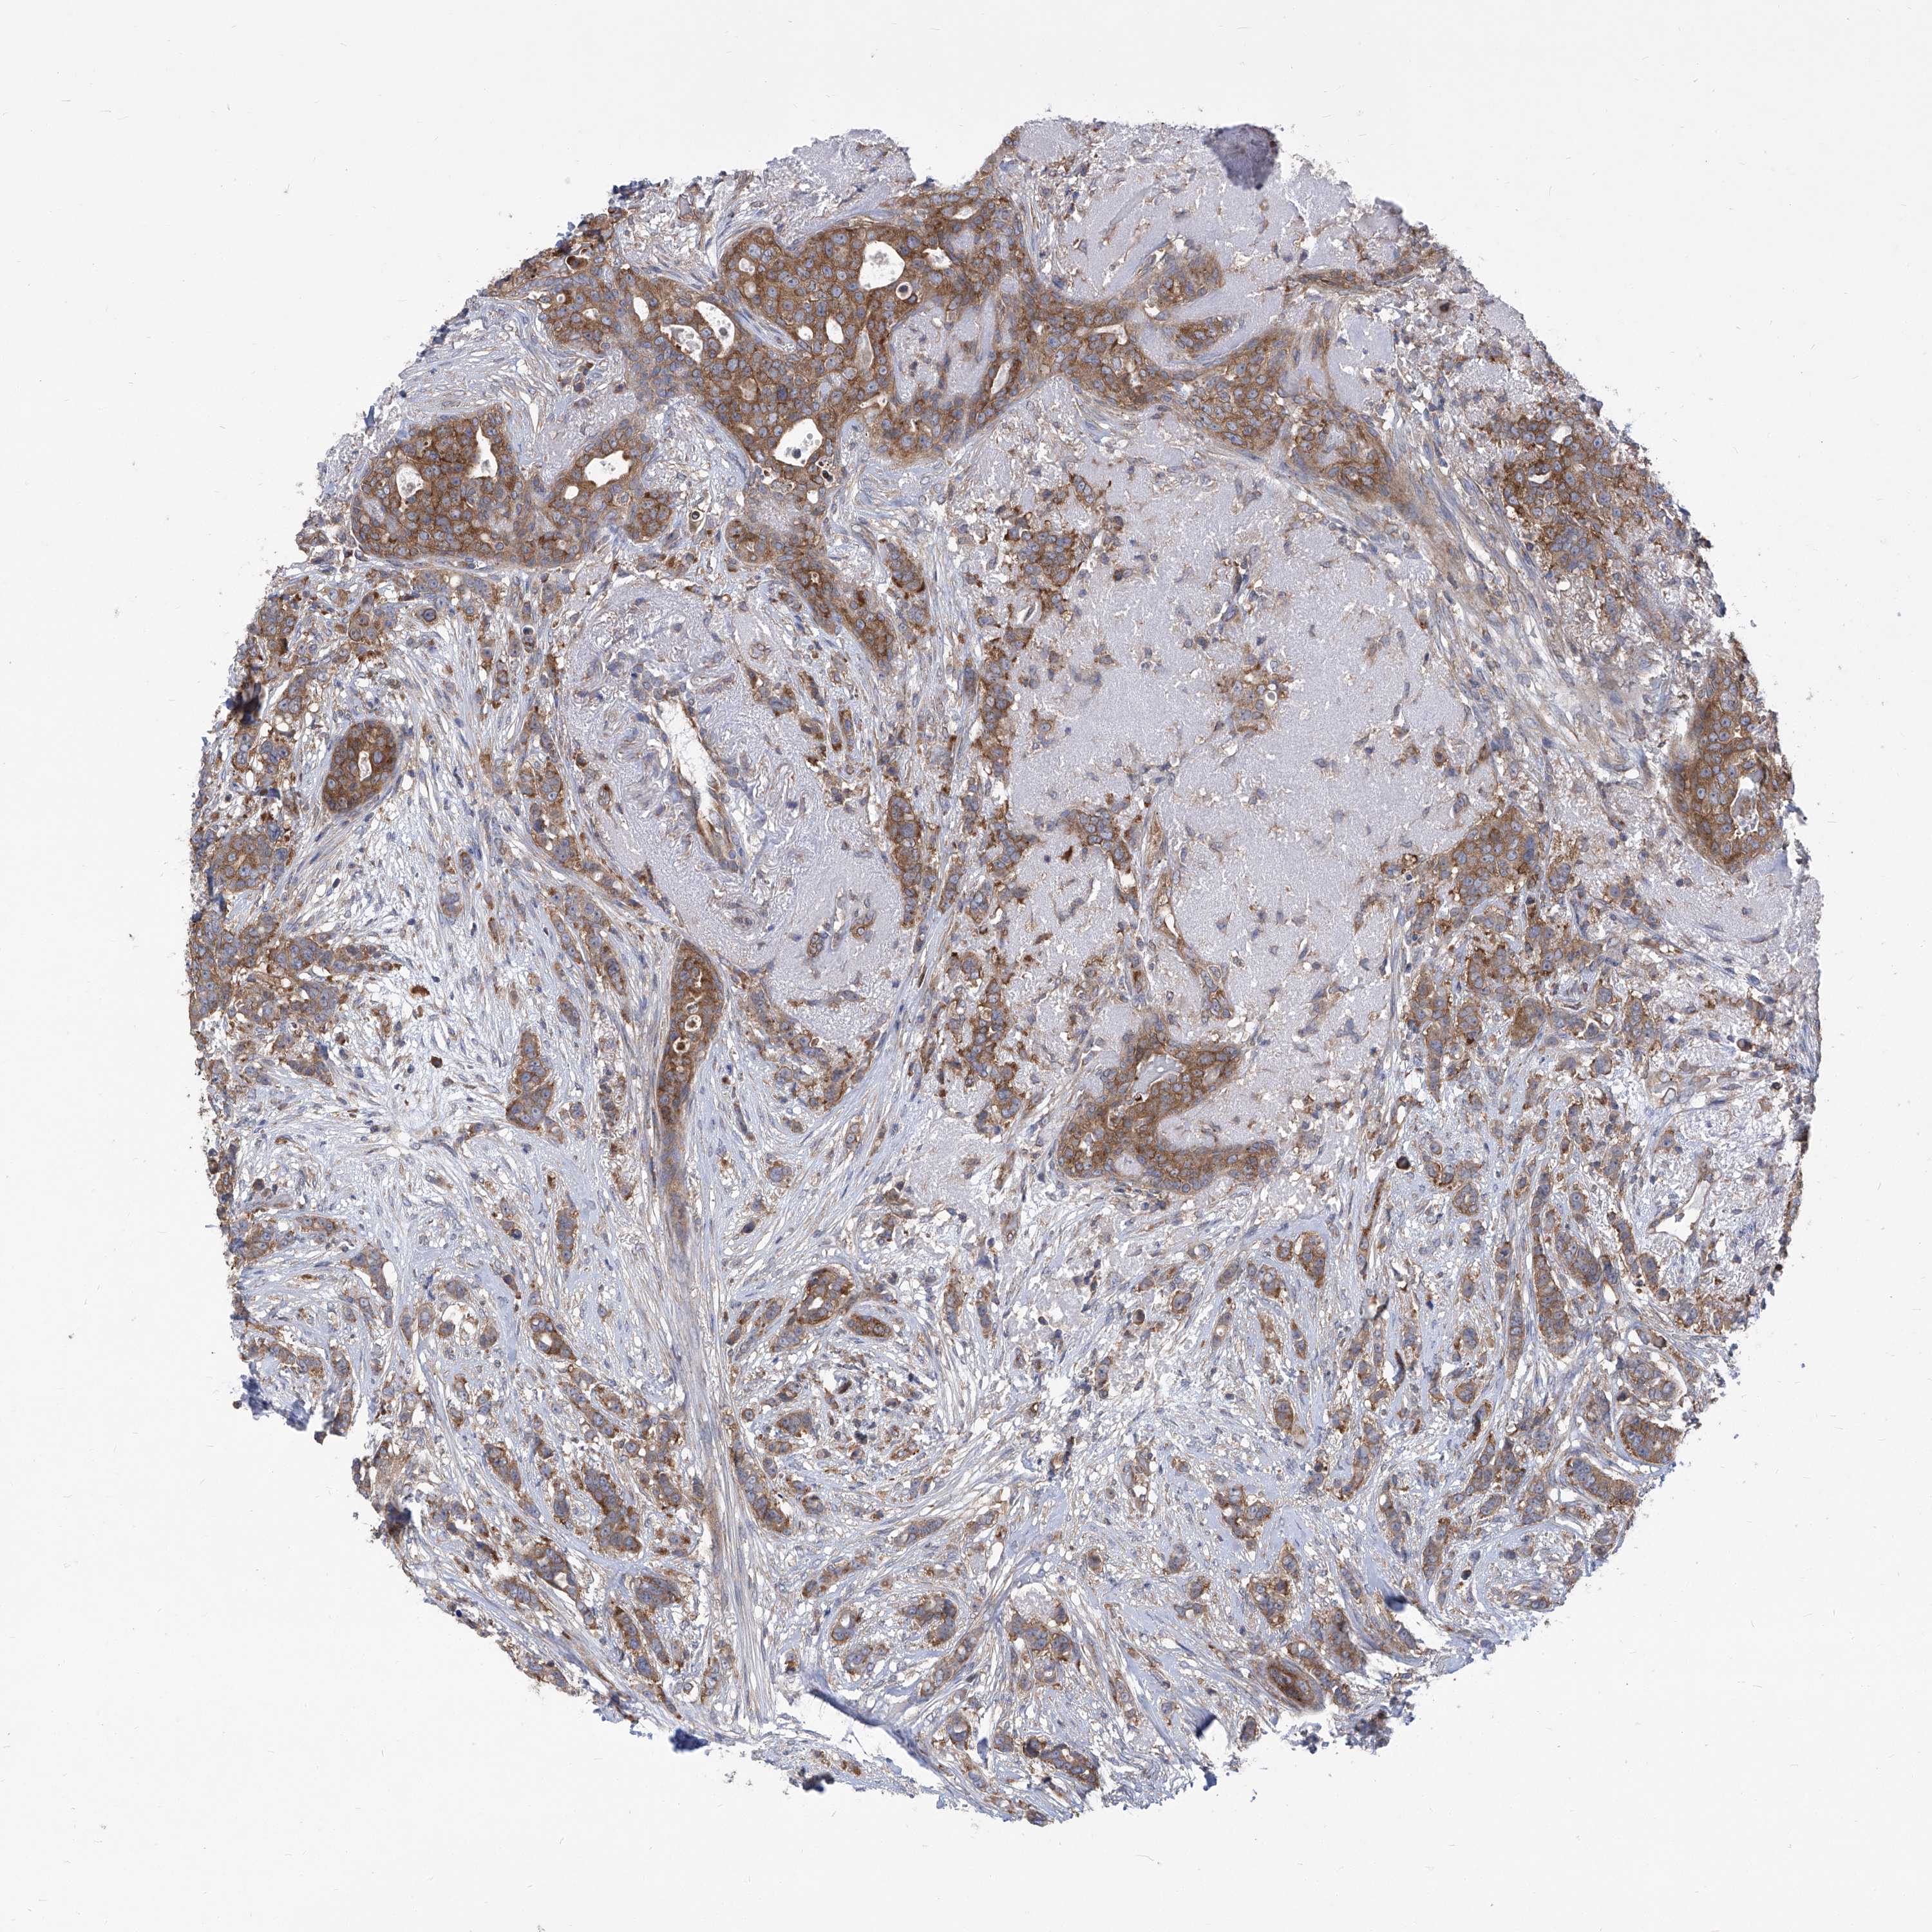

BRCA TCGA BRCA VALIDATION PROTEIN EXPRESSION